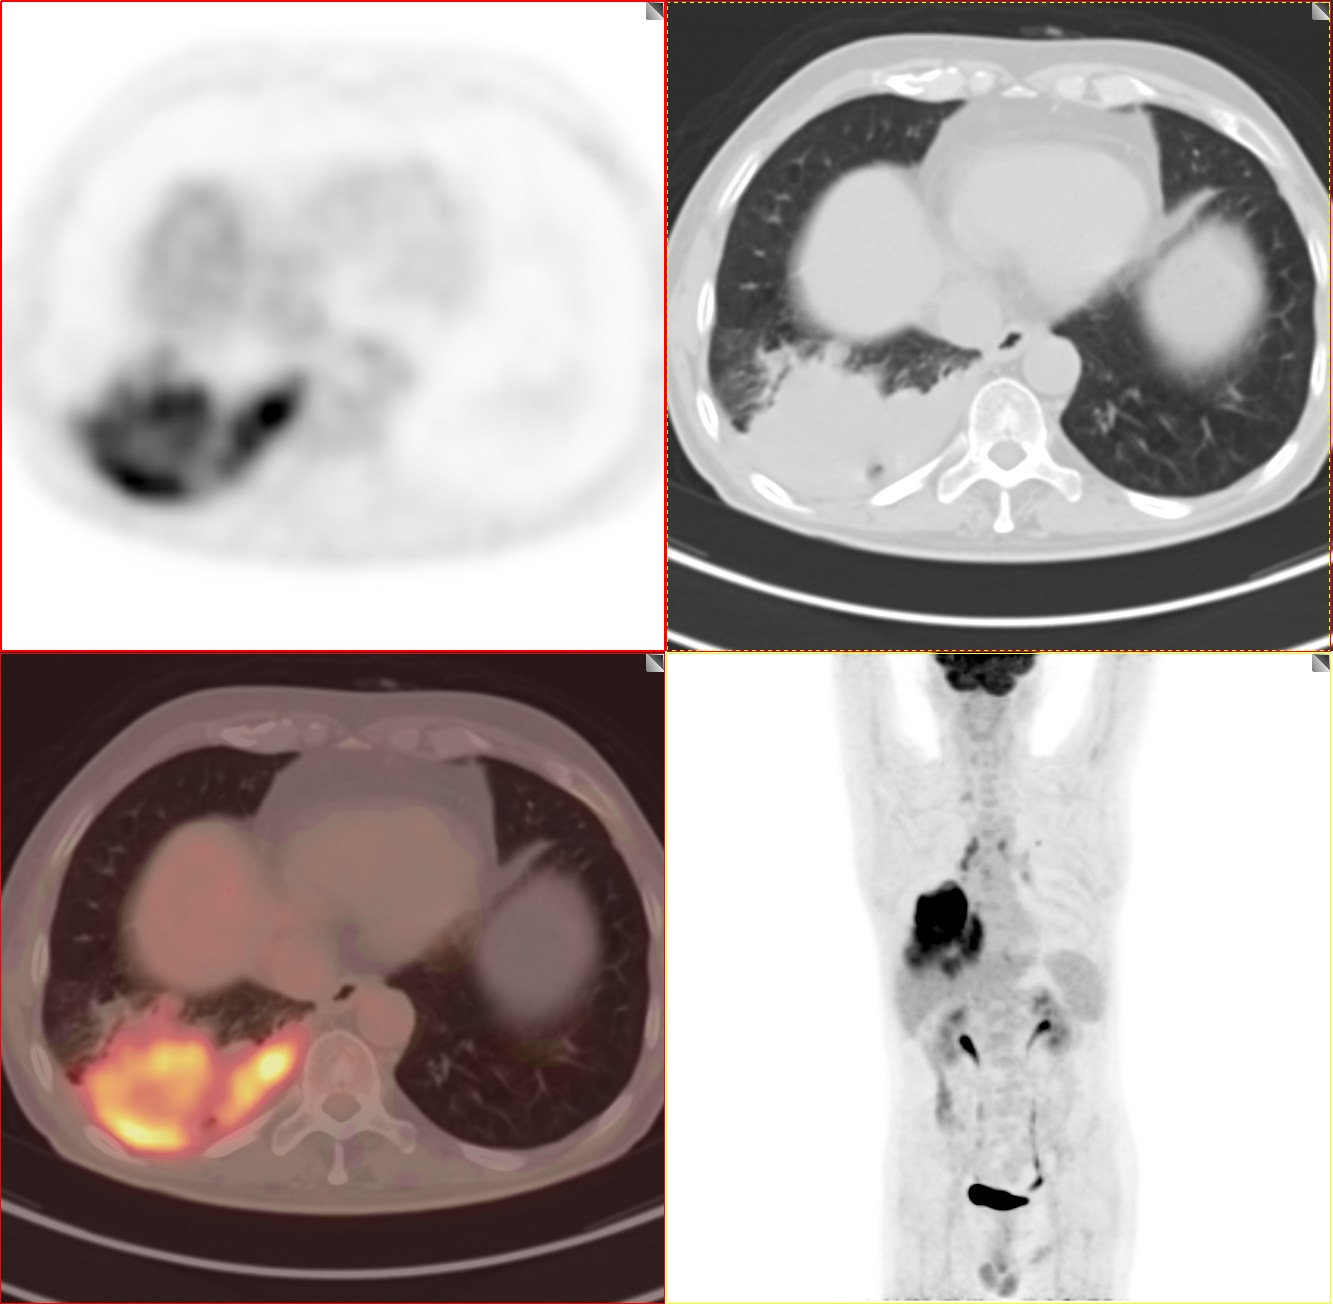

依据影像学分期,该患者后续进行了综合治疗:免疫+化疗+靶向治疗,其中化疗3期,免疫治疗2期及靶向治疗。3个月后患者再次进行了PET/CT检查,对治疗效果进行了评估。2021年11月PET/CT检查结果:

肿瘤病灶明显缩小、实性成分明显减少,肿瘤FDG代谢明显减低,相邻胸膜浸润明显改善,已经没有胸水征象。另外,全身其他部位未见明确转移性病变。

上面两张为治疗后,下面为治疗前

复查后PET/CT诊断:右肺下肺癌综合治疗后,肿瘤病灶明显缩小,FDG代谢明显减低,相邻胸膜未见高代谢病变,考虑肿瘤治疗后疗效显著,仅少量肿瘤活性残留。